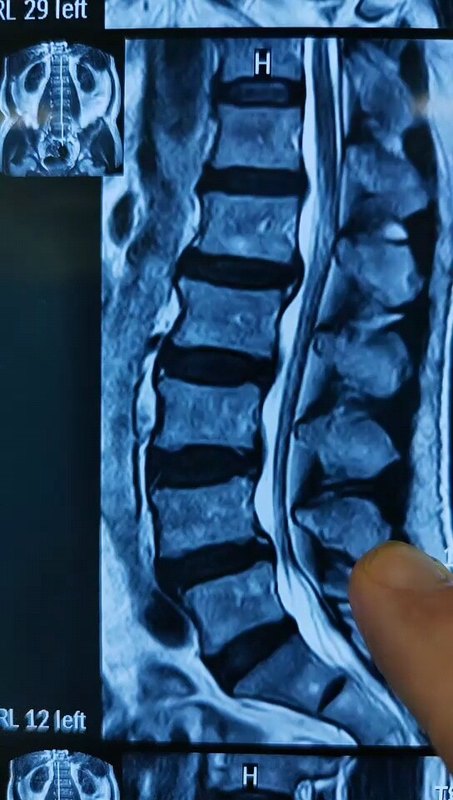

腰椎峡部裂,三十多岁生了8孩子出现腰椎Ⅲ度滑脱

刘江鹏副主任医师 中国人民解放军海军陆战队医院 脊柱外科

103人已读